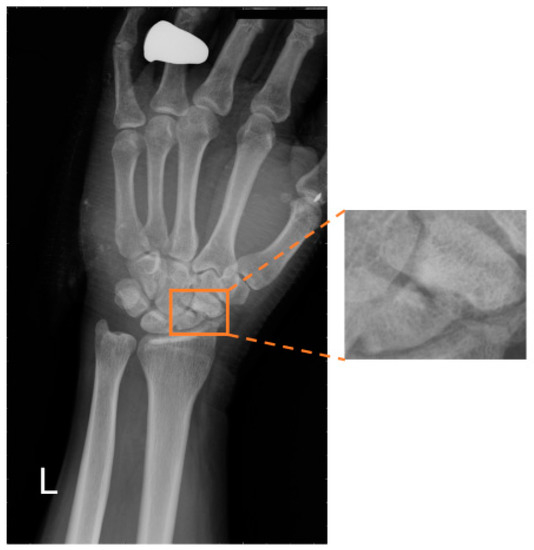

To date, artificial intelligence (AI) has advanced technologies worldwide, successfully being applied in many fields such as industry, commerce, agriculture, smart life, medical informatics, and so on. In these fields, image recognition is widely used to simulate human vision (so-called computer vision). In traditional computer vision, an image can be described by its color, texture, and shape; thereby, the objects in an image can be recognized by machine learning methods. However, the effectiveness of such approaches is limited in incomplete feature analysis. To address such problems, deep learning (DL) has been proposed as a solution, which can be viewed as a set of neural networks based on human neural biology and which can recognize objects by conducting iterative feature filtering. In fact, DL has been shown to be effective for the diagnosis of cancer and fractures. For example, several online systems that allow the user to submit an image to detect the carcinomas have been developed. Normally, the accuracy can reach around 95%. In biomechanics, deep learning has been successfully used to detect general fractures in bioimages, including those in the axial skeleton, appendicular skeleton, skull, spine, ribs, sternum, and so on. Few previous studies have focused on scaphoid fracture detection. As shown in Figure 1, the scaphoid bone is one of the eight bones of the wrist and is the most common location for carpal fractures (i.e., about 70% of carpal fractures). Scaphoid fractures are mostly caused by the palms supporting the ground when falling, such that the wrists are excessively squeezed. Patients often have the wrist pain on the thumb side; this pain is especially intense during rotation. As the bone structure of the wrist is delicate and complex, it is not easy to discover the deformity from the appearance of the fracture, that is, if the fracture does not have much displacement, traditional X-ray examination often causes misjudgments and, thus, delay of treatment.

Figure 1. Example of the scaphoid bone.